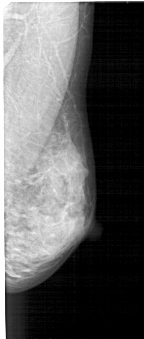

A_1446_1.RIGHT_CC

RIGHT_MLO LINES 5071 PIXELS_PER_LINE 2146 BITS_PER_PIXEL 12 RESOLUTION 43.5 NON_OVERLAY